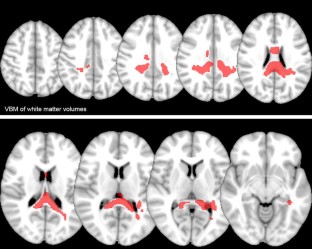

Hereditary spastic paraplegias (HSP) are a group of clinically and genetically heterogeneous disorders with the hallmark of progressive spastic gait disturbance. We used advanced neuroimaging to identify brain regions involved in SPG4, the most common HSP genotype. Additionally, we analyzed correlations between imaging and clinical findings. We performed 3T MRI scans including isotropic high-resolution 3D T1, T2-FLAIR, and DTI sequences in 15 adult patients with genetically confirmed SPG4 and 15 age- and sex-matched healthy controls. Brain volume loss of gray and white matter was evaluated through voxel-based morphometry (VBM) for supra- and infratentorial regions separately. DTI maps of axial diffusivity (AD), radial diffusivity (RD), mean diffusivity (MD), fractional anisotropy (FA), and measured anisotropy (MA1) were analyzed through tract-based special statistics (TBSS). VBM and TBSS revealed a widespread affection of gray and white matter in SPG4 including the corpus callosum, medio-dorsal thalamus, parieto-occipital regions, upper brainstem, cerebellum, and corticospinal tract. Significant correlations with correlation coefficients r > 0.6 between clinical data and DTI findings could be demonstrated for disease duration and disease severity as assessed by the spastic paraplegia rating scale for the pontine crossing tract (AD) and the corpus callosum (RD and FA). Imaging also provided evidence that SPG4 underlies a primarily axonal rather than demyelinating damage in accordance with post-mortem data. DTI is an attractive tool to assess subclinical affection in SPG4. The correlation of imaging findings with disease duration and severity suggests AD, RD, and FA as potential progression markers in interventional studies.